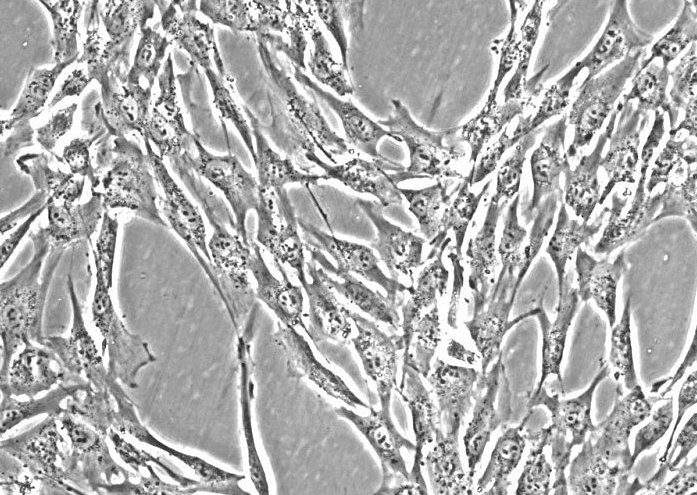

Caco-2

贴壁细胞

上皮细胞样

1.产品名称:Caco-2人结肠癌细胞(通过STR鉴定)

2.组织来源:结肠,结直肠腺癌